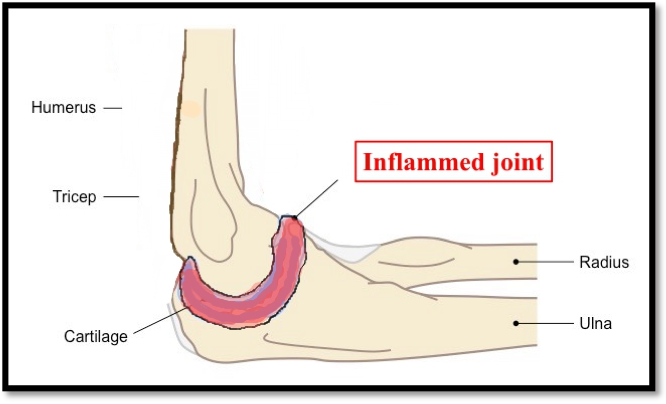

Sometimes there is inflammation or infection in the elbow joint which

• Cannot be diagnosed by blood tests and radiological tests like MRI.

• Cannot be treated completely by medicines.

Patients have pain in the elbow, which increases with all movements of the elbow, sometimes elbow is fixed in one position; with or without fever. If there is infection, the symptoms start and progress very rapidly within 1-2 days with very high-grade fever and patient is very unwell. Often patients with more chronic problems have undergone multiple MRI and other investigations without pain relief.

3. How can arthroscopy help in these cases?

n these cases an elbow arthroscopy is useful to obtain tissue directly from the elbow for diagnosis. Although this is not the treatment it does help to get a diagnosis. Elbow arthroscopy is also useful to remove the inflamed tissue or the infected tissue as a part of the whole treatment process.